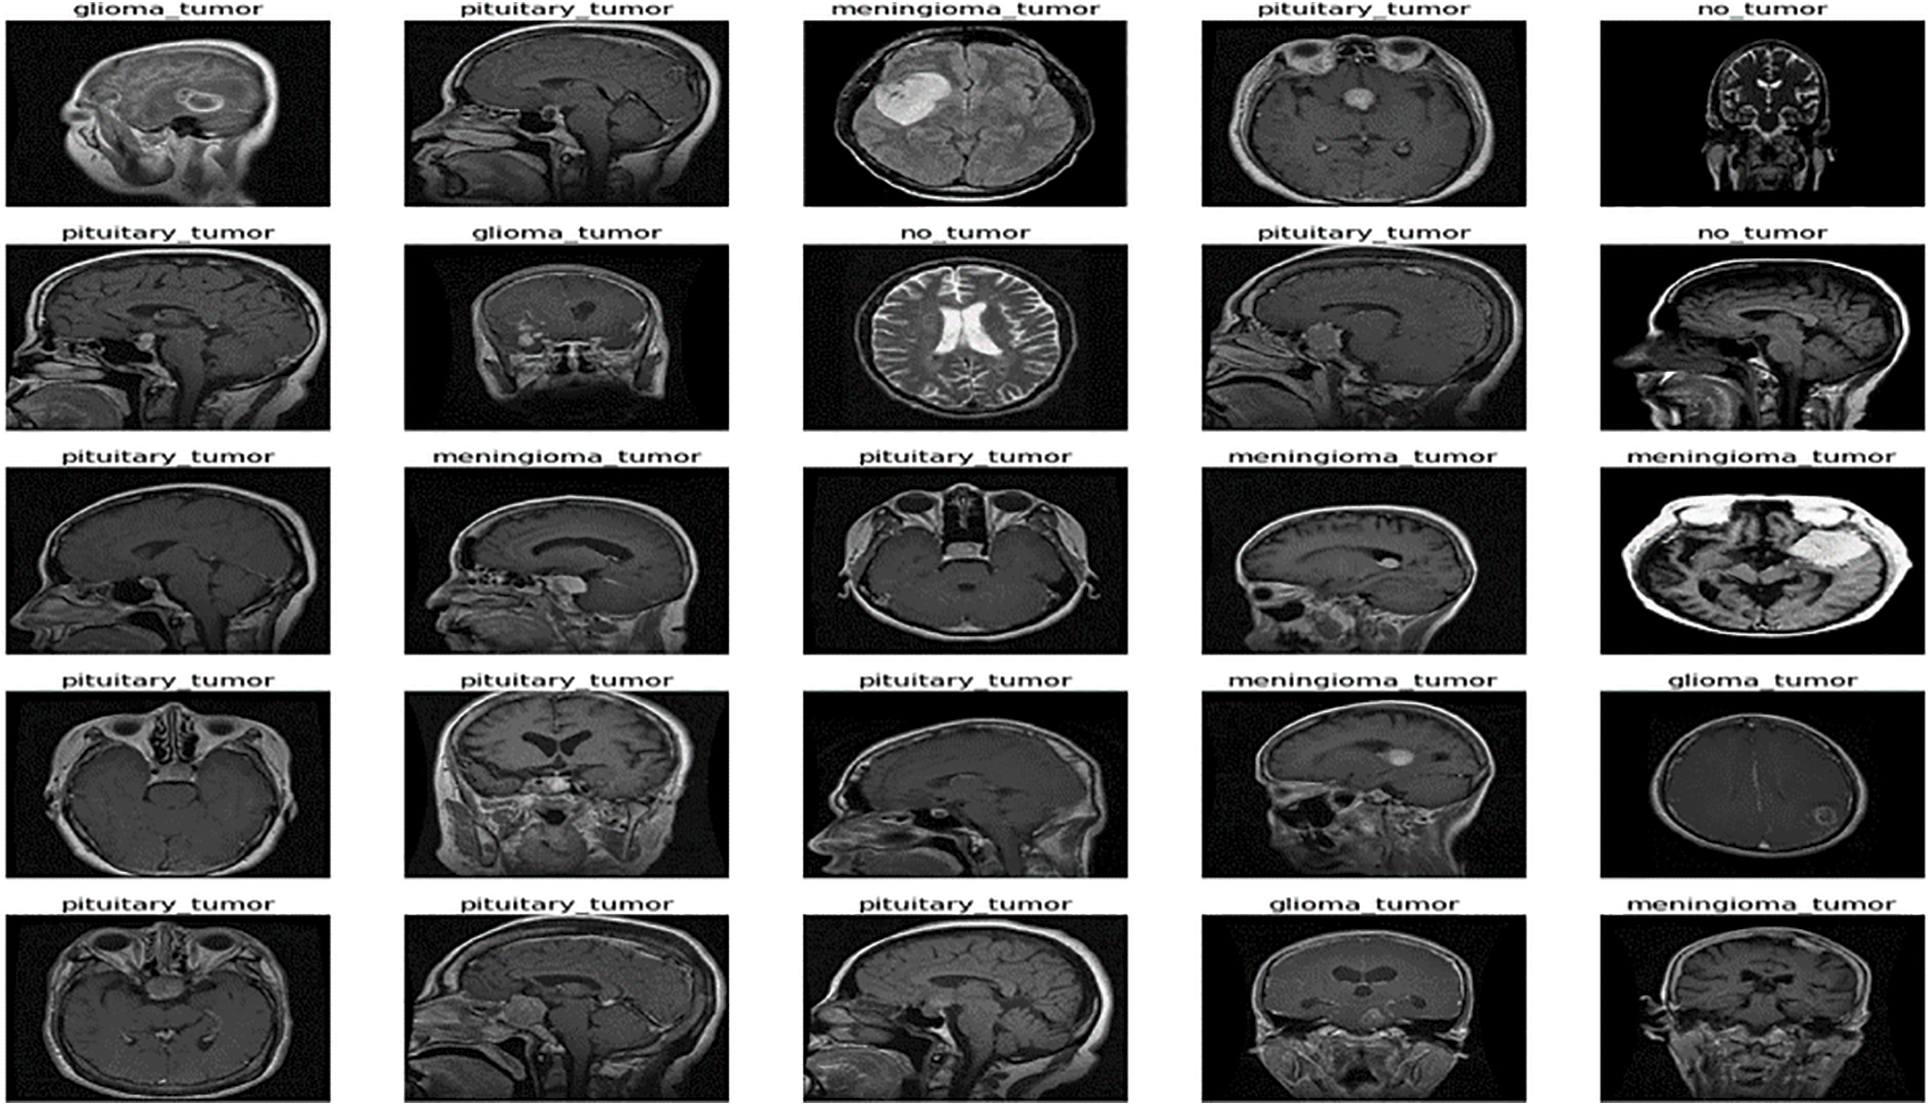

The freely accessible CE-MRI dataset (https://figshare.com/articles/braintumor dataset/1512427) has been used. It consists of 2-dimensional images with a large slice gape. The dataset was collected from 2005 to 2020 from different hospitals in China. The dataset consists of four tumor classes: glioma, meningioma, pituitary, and no tumor [45], as revealed in Fig. 4. A glioma tumor is a common brain tumor that originates in the glial tissues surrounded by neurons [46].

Figure 4: Sample images of CE-MRI dataset

In contrast, meningioma is a tumor that arises from meninges tissues surrounding the brain and spinal cardinal system [47]. A pituitary tumor is due to the abnormal growth of pituitary glands in the back of the nose [48]. The size of each image in the dataset is 512 × 512 pixels, as shown in Fig. 2. The CE-MRI dataset was separated into training 70%, validation 15%, and testing 15%. The description of dataset is given below in Tab. 3.

The images in the dataset are 2-dimensional with 512 × 512 pixels, as shown in Fig. 4. The dataset is checked with duplication, missing values, label name, and extension during the cleaning. Moreover, all the images are made noise-free using a histogram equalizer. In this work, the images are directly fed to the convolutional neural network, and the kernel is applied to resize the images. The results are highly dependent on these values. However, these values are not fixed and vary according to the image pixel sizes. To remove these intensity variations, normalization is used. So before giving values to the CNN model, all the values are normalized, having the same size range. Now the size of the images is 224 × 224 after normalization and resizing. In this way, the training process speeds up by resizing images and requires less memory.